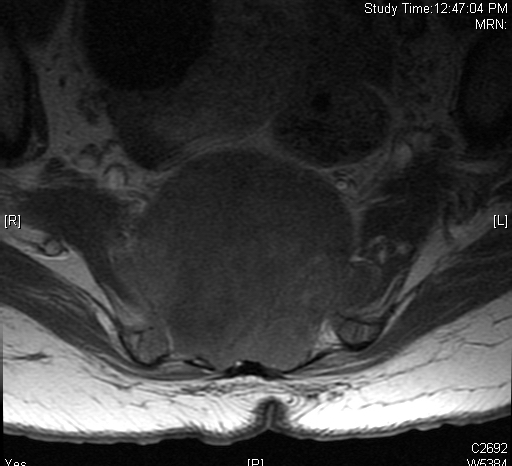

MRI (Fig. 4-10)

• Isointense or hypointense on T1W (Fig. 4-5)

• Hyperintense on T2W (Fig. 8 & 9)

• Hyper enhancement with gadolinium (Fig. 6 & 7).

Fig. 4-10: MR image of a chordoma shows a destructive bone lesion in the sacrum that is hypointense on T1W images, hyperintense signal on T2W and enhancement of the lesion after gadolinium.